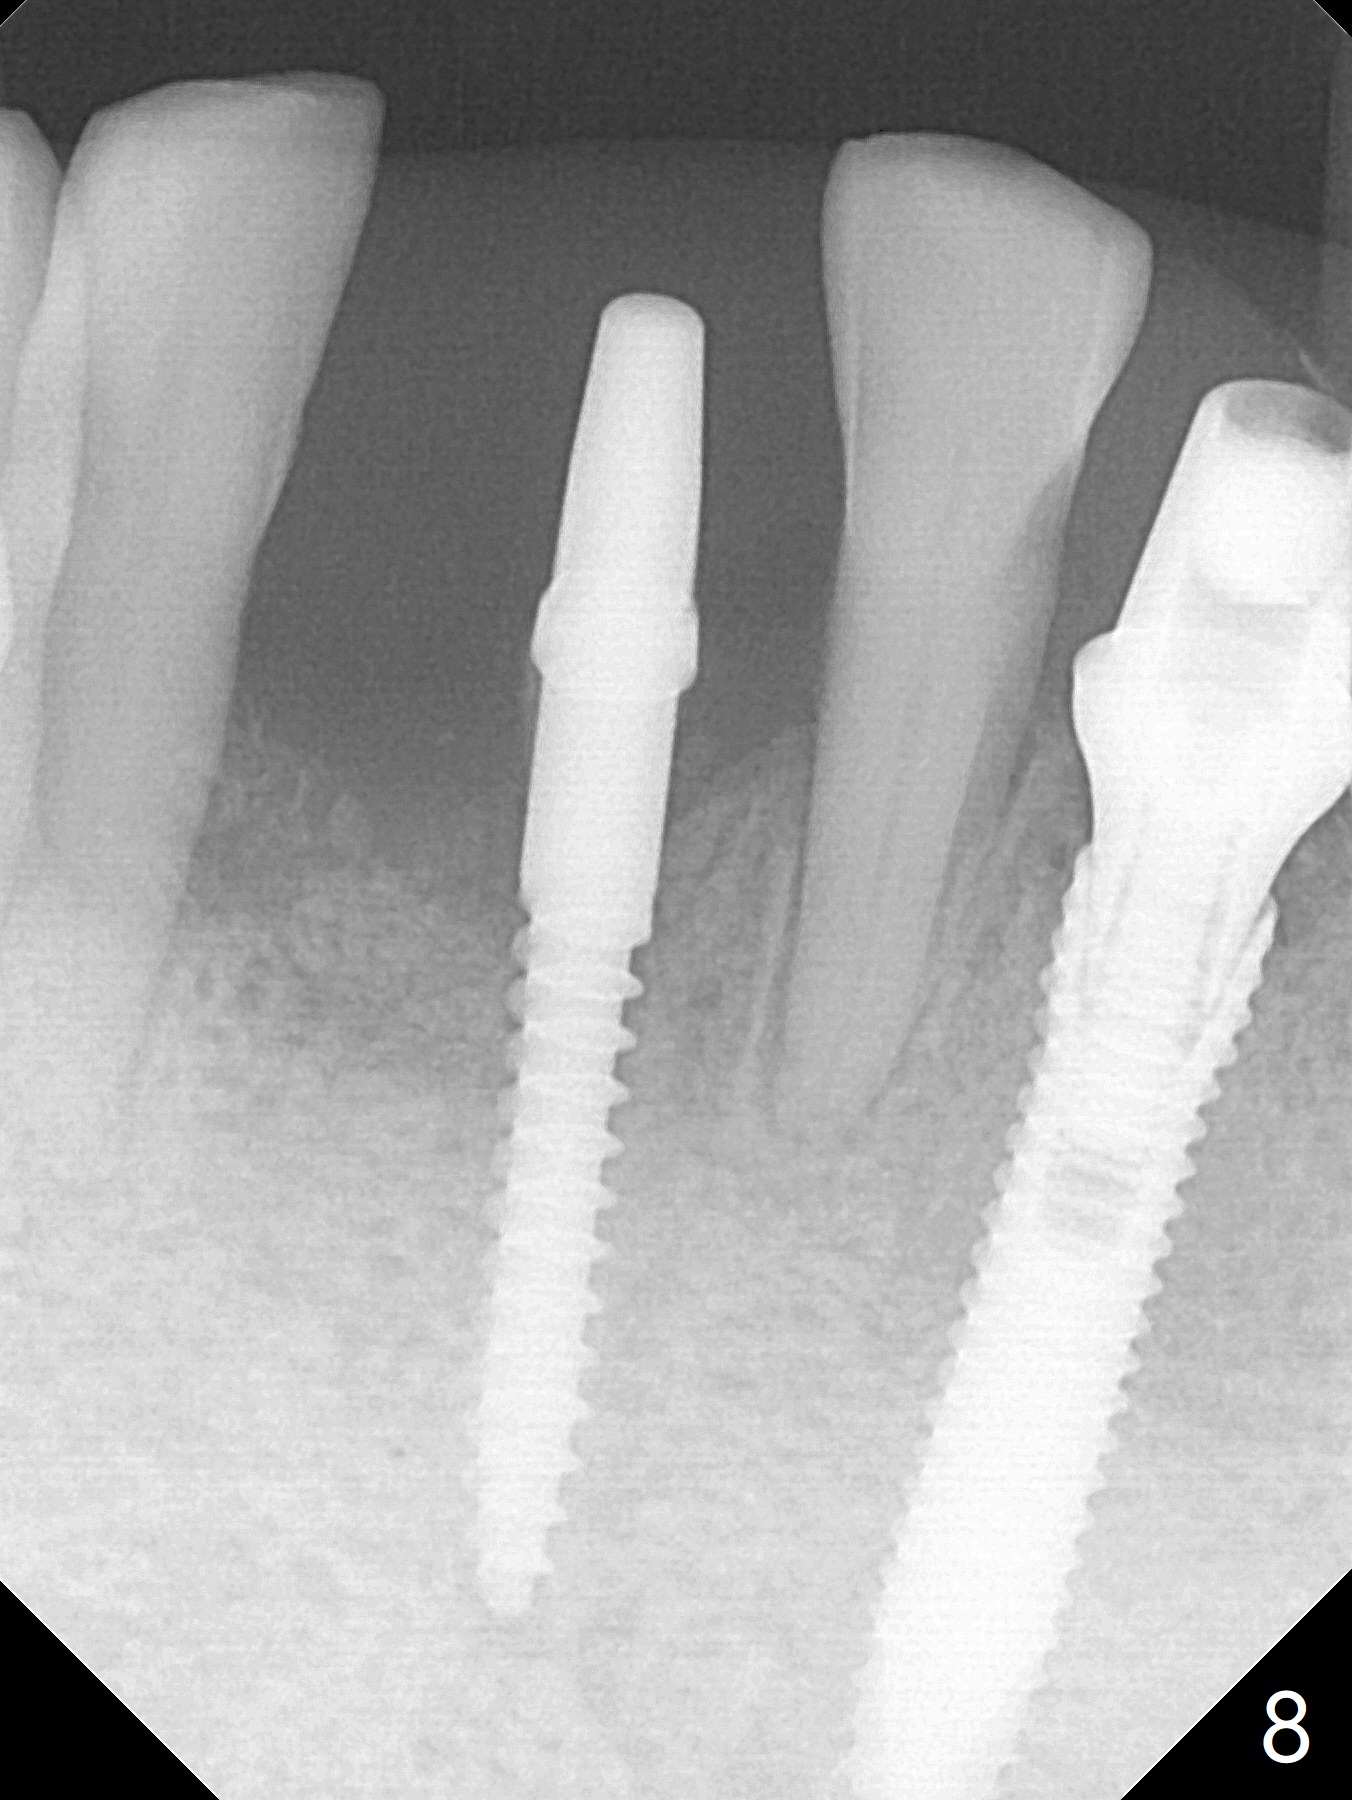

The depth of the osteotomy at #22 is 2-3 mm more than the expected implant length (Fig.2 with 2.7 mm drill in place). The implant at #22 (3.8x18 mm with insertion torque more than 50 Ncm) has clearance from the Incisive Canal and Mental Loop (Fig.3 red dashed line). Allograft with Osteogen is placed around the implants (Fig.4 *) in addition to Osteogen plug (cut in a thin layer) placed against the buccal wall of the socket at #22 (potential leakage). After suturing (Fig.5) and provisional cementation (Fig.6), periodontal dressing is applied (Fig.7). The implants seem to be ready for impression 4 months postop (Fig.8).